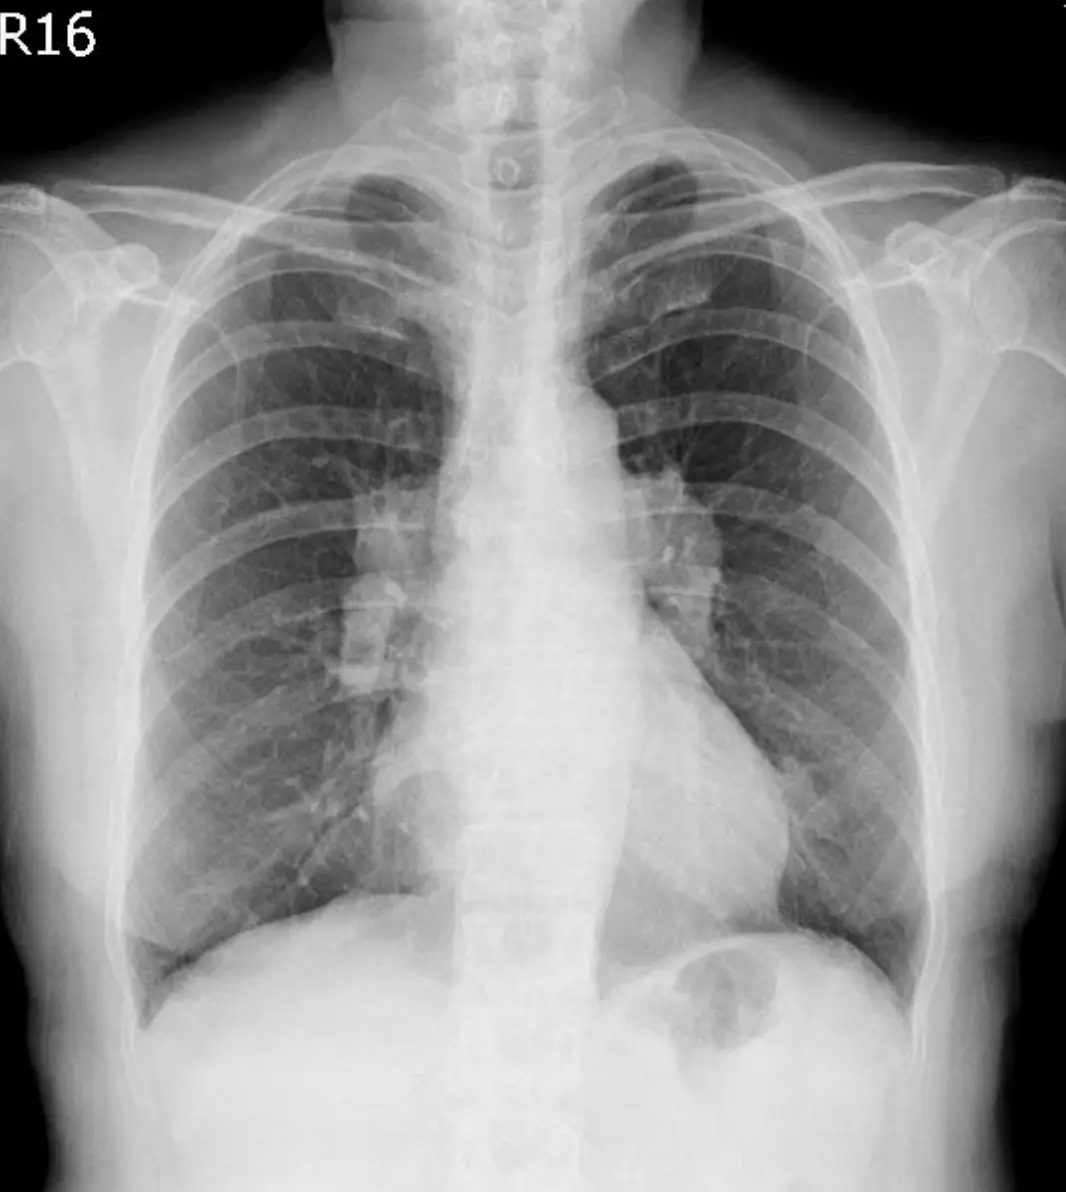

- 胸部X光(直立後前位):

- 雙側肺門(hilar)明顯腫大,形態對稱,未見明顯肺野浸潤或局部實變。

- 右側上縱隔亦可見輕度腫大。

- 無肋間隙擴張或其他累及肺野的廣泛浸潤影。